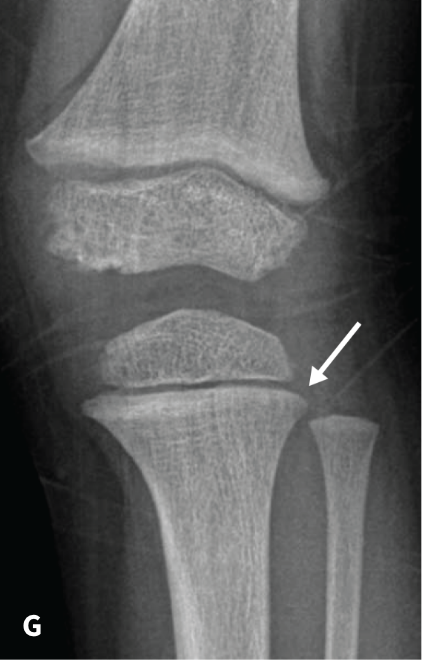

The RSS is a quantitative method that uses radiographs to assess the severity of rickets at the wrists and knees. Originally validated in nutritional rickets, the score is based on the degree of metaphyseal fraying, metaphyseal cupping, and the proportion of the growth plate that is affected. It is a 10-point scale, for which 10 represents the most severe radiographic changes due to rickets and 0 represents the absence of these changes.1

Although the severity and duration of rickets vary considerably between XLH and nutritional rickets, the radiographic features of rickets at the growth plate are similar in the two disorders, which allowed validation of the RSS in XLH. The RSS correlates with serum alkaline phosphatase (ALP) levels, a biochemical marker of rachitic activity, and this scoring system can be used to assess the radiographic response following treatment of nutritional or XLH rickets.

The RSS in XLH has been reported to range from 0 to 4.5; however, despite the smaller RSS range observed in XLH patients, inter- and intra-rater reliability are similar to those reported for nutritional rickets. Patients with XLH who had a baseline RSS ≥1.5 were shown to have more severe hypophosphatemic bone disease, including higher levels of alkaline phosphatase, and greater impairments in clinical outcomes compared with patients who had a baseline RSS <1.5.